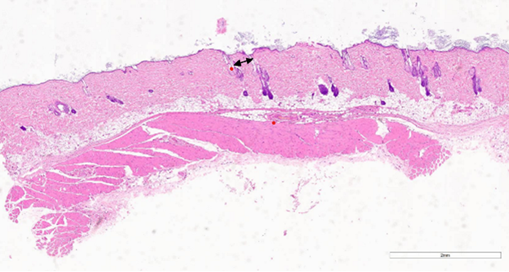

Рис. 7. Уменьшение количества сально-волосяных комплексов на 47-й день после процедуры воздействия CO2-лазером. Окрашивание гематоксилином и эозином (х5). Примечание: рисунок составлен авторами по результатам данного исследования

При проведении гистологического исследования образцов, полученных у особей из группы 2, можно проследить наличие очагового истончения эпидермиса и фиброза (рис.8) при выраженном уменьшении количества сально-волосяных комплексов (рис.9). Вместе с тем у одной из особей группы2 можно наблюдать отсутствие морфологических изменений в дерме, которые могли бы указывать на эффект энергетического воздействия (рис.10).